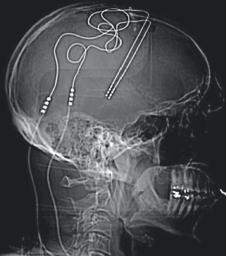

近日,“全球首例!脑电刺激成功拯救重度抑郁症患者,治愈抑郁症时代离我们不远了?”新闻刷屏。美国加州大学旧金山分校的研究团队在《Nature Medicine》期刊发表论文,总结了他们通过深部脑电刺激(见图1)让一名重度抑郁症患者病症得到了很大程度缓解的方法。

图1 DBS装置安装图

深部脑电刺激(deep brain stimulation,DBS),指的是一种涉及放置神经刺激器(又称“脑起搏器”)的神经外科手术。它通过大脑深处特定部位的植入电极,将高频电脉冲发送到特定大脑区域,通过控制脑外的脉冲发生器来操控大脑的神经活动。

图2 如筷子样的为刺激电极,与之相连的为导线,脉冲发生器在脑外